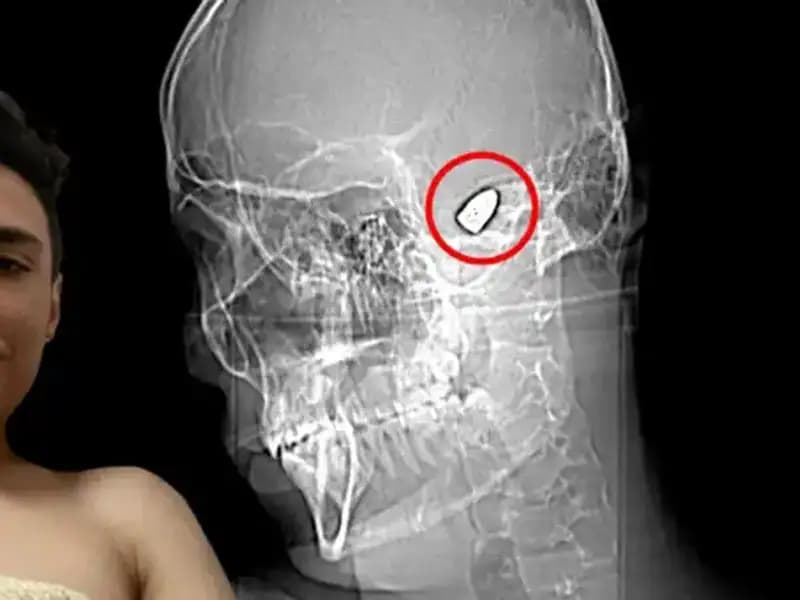

Hayatının bir döneminde yaşadığı bir kaza sonucunda, 35 yaşındaki emekli bir asker olan Mehmet, kafasında bir patlayıcı cihaz taşımaya başladı. Savaş yıllarında başına gelen bir olay sonucu, kafasında yerleştirilen bu düzenek, artık onun ayrılmaz bir parçası haline gelmişti. Mehmet, bu durumu hem fiziksel hem de ruhsal olarak taşımakta zorlanıyordu. Her an patlayabileceği korkusuyla yaşamak, onun için yalnızca bir kabus değil, aynı zamanda her gün yaşadığı gerçek bir tehlike haline gelmişti.

Günlük yaşamında, alışverişe çıkmak, arkadaşlarıyla buluşmak veya yalnızca yürüyüşe çıkmak bile bir cesaret işi olmuştu. Kendisi gibi düşünen insanlarla bir araya gelmek, olası tehditleri azaltmak adına ona bir nebze olsun rahatlık sağlarken, yine de her an bir anksiyete krizine kapılma ihtimaliyle yüzleşmek zorundaydı. Kafasında taşıdığı bu tehlike, herhangi bir an için patlamaya hazır bir bomba gibiydi. Bu da doğal olarak birçok sosyal kaygıyı beraberinde getiriyordu.